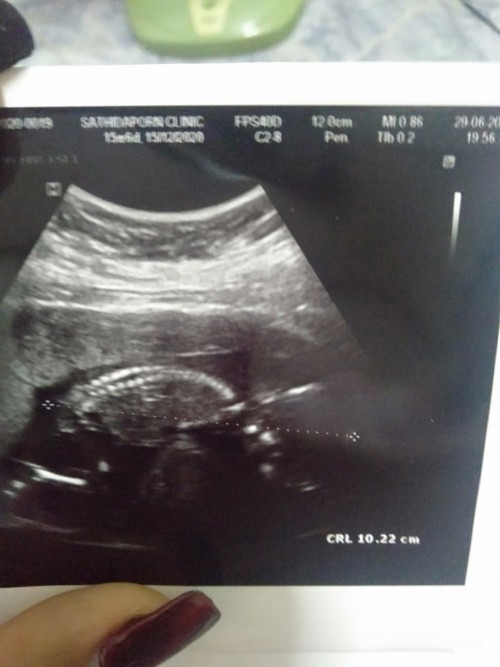

น้องนอนคว่ำแบบนี้ปกติมั้ยค่ะ? แอบกังวล

ซาวด์มารอบล่าสุด นอนท่าเดียวกันเลยคุณแม่ ตอนแรกก็กังวลเหมือนกันค่ะ แต่คิดว่าเค้าน่าจะดิ้นๆเดี๋ยวก็กลับตัวมั้ง